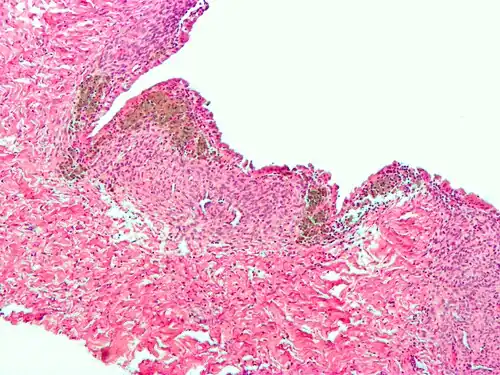

For a histopathological diagnosis, at least two of the following three criteria should be present:[121]

- Endometrial type stroma

- Endometrial epithelium with glands

- Evidence of chronic hemorrhage, mainly hemosiderin deposits

Immunohistochemistry is useful in diagnosing endometriosis as stromal cells have a peculiar surface antigen, CD10, thus allowing the pathologist go straight to a staining area and confirm the presence of stromal cells and sometimes glandular tissue is identified that was missed on routine H&E staining.[122]

Endometriosis, abdominal wall -

Micrograph of the wall of an endometrioma. All features of endometriosis are present (endometrial glands, endometrial stroma and hemosiderin-laden macrophages).